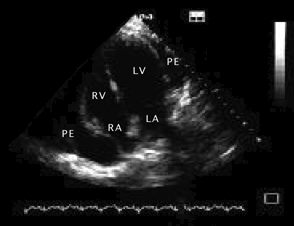

Semne ecocardiografice:

lichid pericardic in cantitate mare (evidentiaza si dispunerea topografica a acestuia),

reducere a amplitudinii excursiei DE si pantei EF a valvei mitrale la prima diastola din inspir,

variatie inspir-expir > 40% a amplitudinii excursiei DE a valvei tricuspide,

colaps AD, VD (protodiastolic) si AS,

congestie 'fixa' a VCI (scadere < 50% in diametru proximal la inspir profund).

EcoCG in tamponada cardiaca